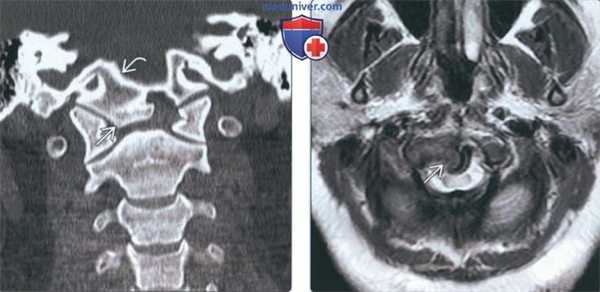

(Слева) На корональной КТ в коаном окне определяется слияние дистопической зубовидной кости со скатом (эксцентрически смещенным вправо).

(Справа) На аксиальной MPT (Т2) определяется патологический сигнал высокой интенсивности в шейном отделе спинного мозга на уровне С1, отражающий его повреждение, обусловленное атланто-аксиальной нестабильностью и легкой гипоплазией С1 в сочетании с эксцентрической птичьей костью.

3. КТ при птичьей кости:

• КТ в костном окне:

о Картина аналогична таковой на рентгенограммах

о Часто наблюдается дисплазия ската

4. МРТ при птичьей кости:

• Т1 ВИ:

о Четко очерченная кость, слившаяся со скатом о Нормальный для губчатого вещества сигнал в зубовидной кости, скате

• Т2 ВИ:

о Картина аналогична Т1 ВИ

о ± контузия спинного мозга, миеломаляция при краниоцервикальной нестабильности